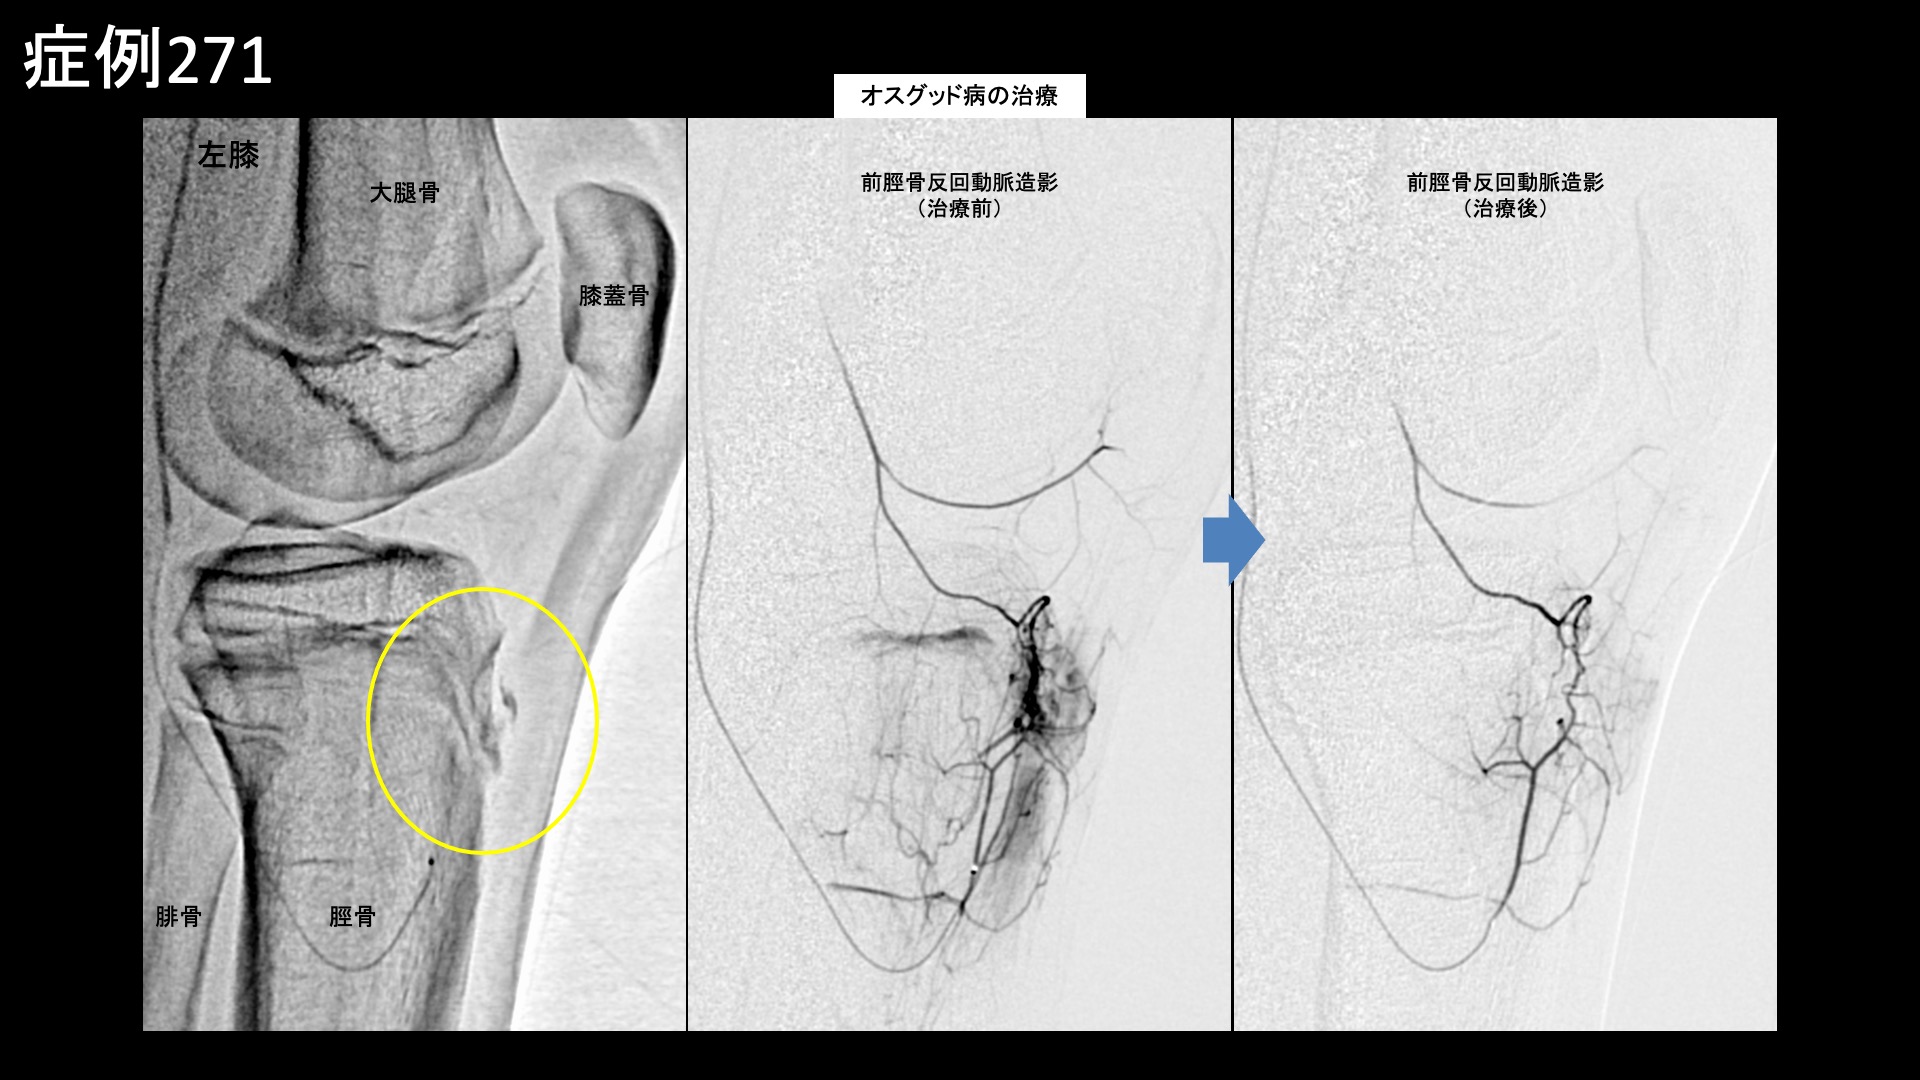

血管造影を行うと、前脛骨反回動脈で同オスグッド部位(膝のお皿の下にある脛骨の先端部分(脛骨粗面))に一致して、モヤモヤ血管が濃染像として描出されました。治療後は画像上速やかに消失しました。その他複数箇所の治療を行い終了しました。

治療前画像:損傷を受ける、あるいは繰り返しのストレスにより発生した異常な新生血管

治療後画像:カテーテルを用いて塞栓物質を血管内に投与し新生血管を塞いだ状態